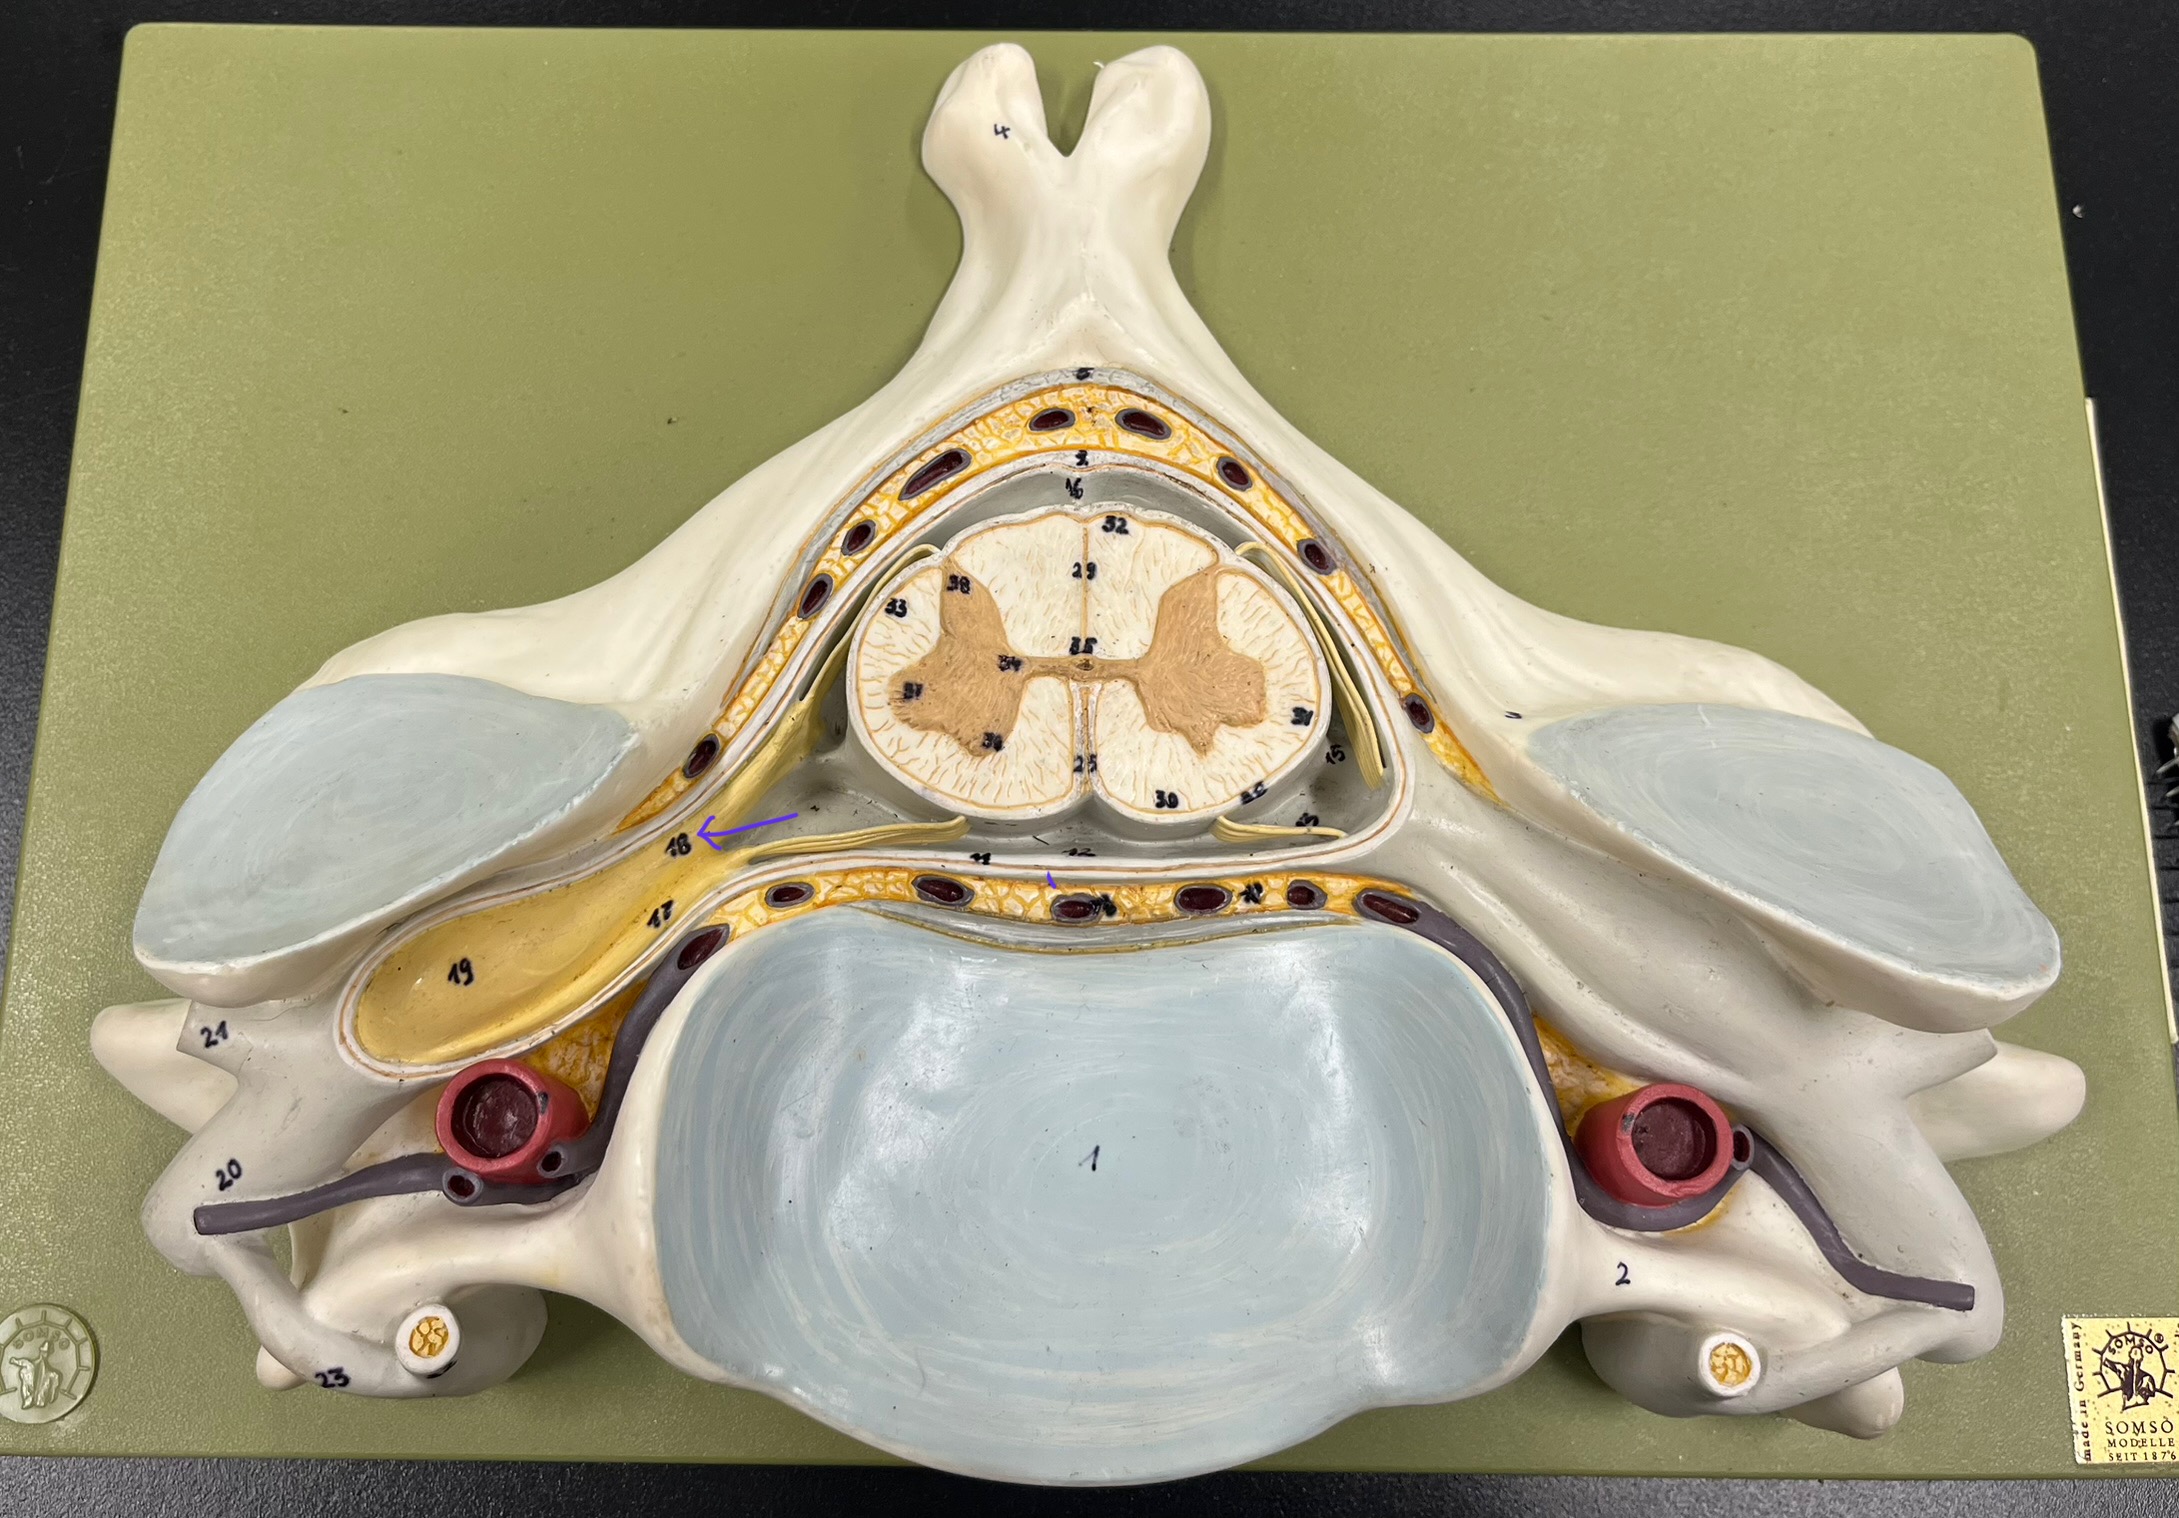

epidural space

dura mater

subdural space

arachnoid mater

subarachnoid space

pia mater

denticulate ligaments

What is the groove here?

anterior median fissure

posterior median sulcus

posterior (dorsal) horn

posterior (dorsal) horn; R—>L

anterior (ventral) horn

lateral horn (selected models)

gray commissure

central canal

anterior column

lateral column

posterior column

white commissure

posterior (dorsal) root ganglion

What is the bulb here?

posterior (dorsal) root ganglion

posterior (dorsal) root

posterior (dorsal) root

anterior (ventral) root

anterior (ventral) root

dorsal ramus

dorsal ramus

ventral ramus

ventral ramus

rami communicantes

rami communicantes

sympathetic chain ganglia

sympathetic chain ganglia